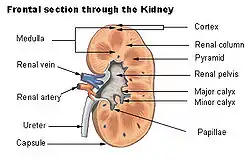

The renal column (or Bertin column, or column of Bertin) is an extension of the renal cortex in between the renal pyramids. It allows the cortex to be better anchored. (Cortical extensions into the medullary space.)

Each column consists of lines of blood vessels and urinary tubes and a fibrous material.